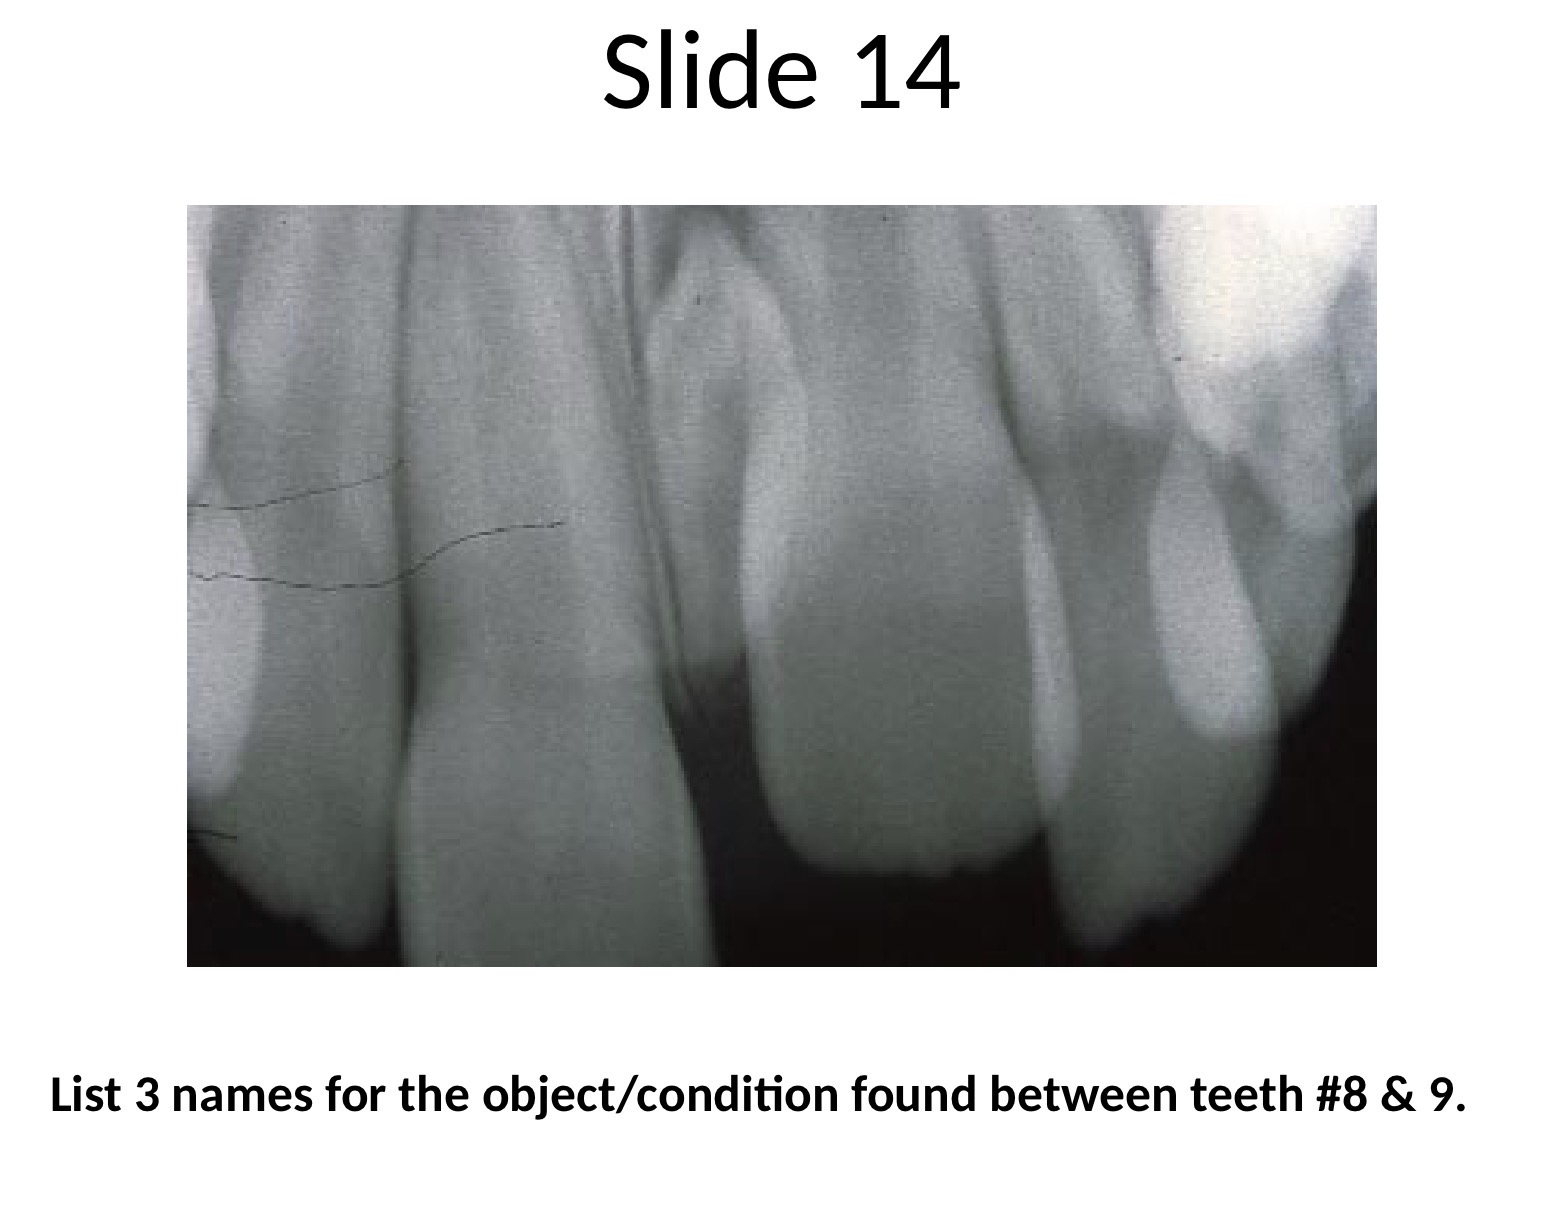

Dens invagiatus, dens in dente

red

enamel organs invaginates into the crowns of the tooth prior to mineralization